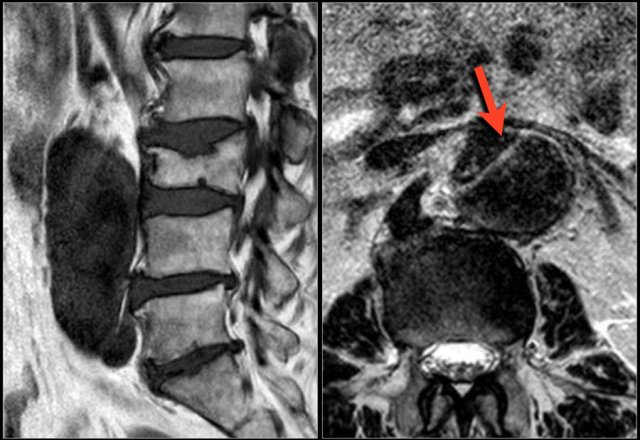

Epidural lipomatosis

Epidural lipomatosis is excessive amount of fat within the epidural space compressing the thecal sac.

Patients present with symptoms of spinal canal stenosis.

It is seen in patients with obesity, like in this case and in patients who are treated with steroids.

Continue with the axial images of this patient.

Scroll through the axial images.

Notice how the spinal canal is narrowed by the epidural fat.

Do not mistake the high signal intensity of the fat for CSF.